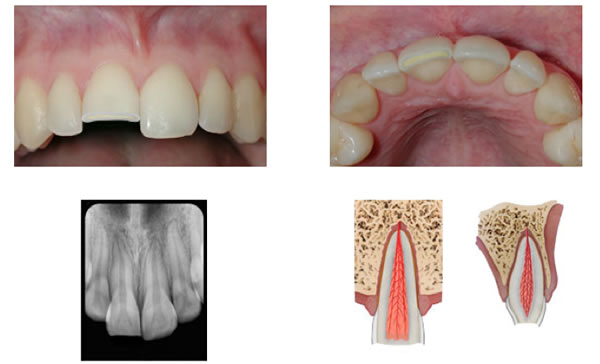

Complicated Crown Fracture

Figure 4. A complicated crown fracture involving enamel, dentin, and the pulp.

Complicated crown fractures involve enamel, dentin, and pulp and pulpal necrosis is imminent without treatment (Figure 4). It is very important for a patient to consult with his/her dentist ASAP in order to allow for the best possible treatment options. Vital pulp therapy (VPT), by way of pulp capping or pulpotomy, is an attempt to maintain the vitality of the pulp tissue and is most successful if attempted ASAP following injury. In mature teeth with closed apices, VPT should be attempted in ideal conditions, however if the pulp cannot be saved, root canal therapy can be performed with a high degree of success. In immature teeth with open apices, VPT should be attempted when at all possible to allow for the continued formation of the root (Apexogenesis). This is extremely important as a tooth with an open apex presents unique challenges for endodontic treatment. The walls are typically divergent at the apex, making proper instrumentation, irrigation, disinfection, and obturation very difficult. Additionally, an incompletely formed root has very thin walls and is at higher risk for fracturing.